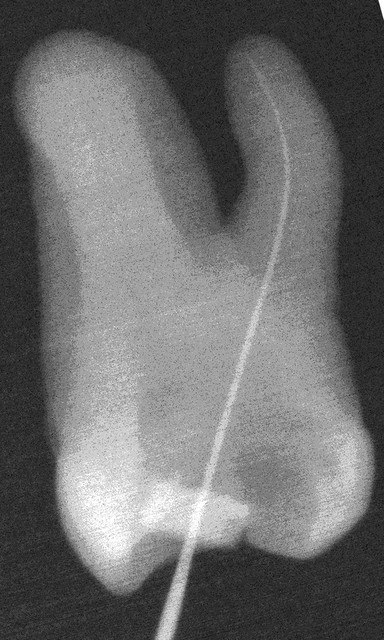

Je voulais tester la fiabilité du localisateur d'apex que je viens d'acheter : l'Ionyx Locapex five ils en sont à leur 5ème version.

une dent avec cavité d'accès trompée à hauteur du collet dans une solution d'hypochlorite 5%.

Les mesures sont effectuées avec une lime O.10

Première mesure : je m'arrête à l'apex que m'indique l'appreil

Je prends des photos et je prend une radio, au constat que la lime dépasse qu'un petit quelque chose je décide de m'arreter à l'indication 0.5 du localisateur d'apex et parraiemment je pends des radios et des photos.

Faut s'arreter bien avant le dernier petit LED qui indique l'Apex sur l'appreil

Désormais j'ai décidé de m'arreter à 0.5